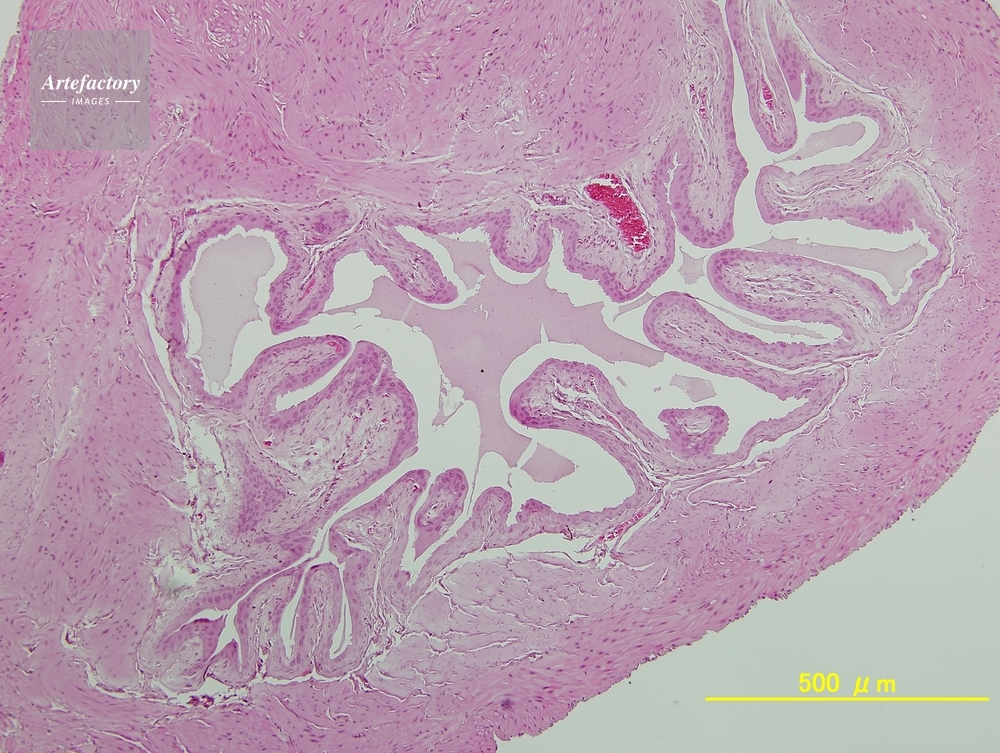

| 作品タイトル | マウス,膀胱 | モデルリリース | なし | |

| 作家 | OLYMPUS CORPORATION Technolab | プロパティリリース | なし | |